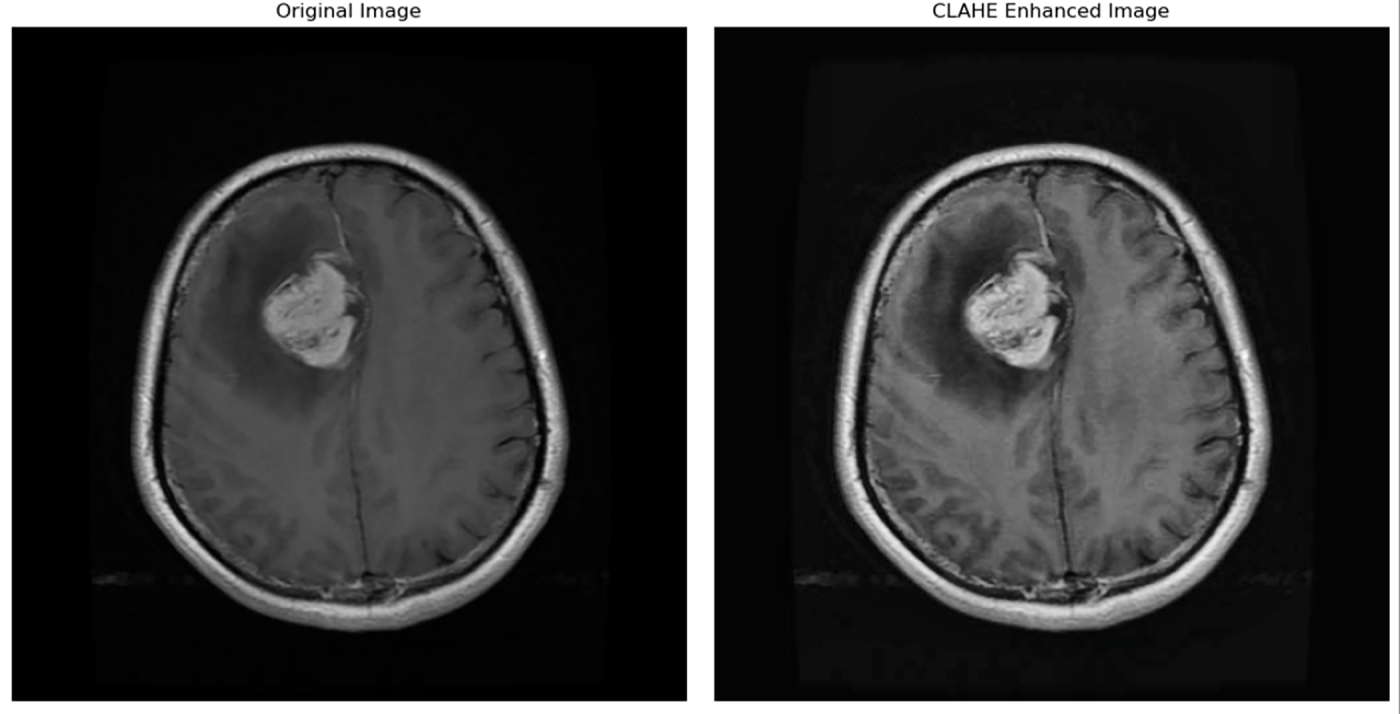

Contrast-limited adaptive histogram equalization (CLAHE) is helpful and greatly effective for low-contrast images, it restrains contrast enhancements in homogeneous areas to avoid noise amplification [26]. Compared to conventional histogram equalization, CLAHE is applied to small regions of the image (tiles). It focuses only on local contrast and may ignore the overall (global) brightness/contrast structure. An application of this algorithm to a medical image is shown in Fig. 5.

Figure 5: Image before and after applying CLAHE [4].

In 1998, Pisano et al. [27] highlighted CLAHE, stating that it constrains noise amplification by clipping the histogram at a specified limit. In medical imaging, where too much noise can mask clinically significant details, this kind of clipping is especially crucial. To maintain significant details in medical imaging, it is essential. Without increasing noise, CLAHE improves visibility by locally enhancing contrast and adjusting to both high-contrast and low-contrast areas.